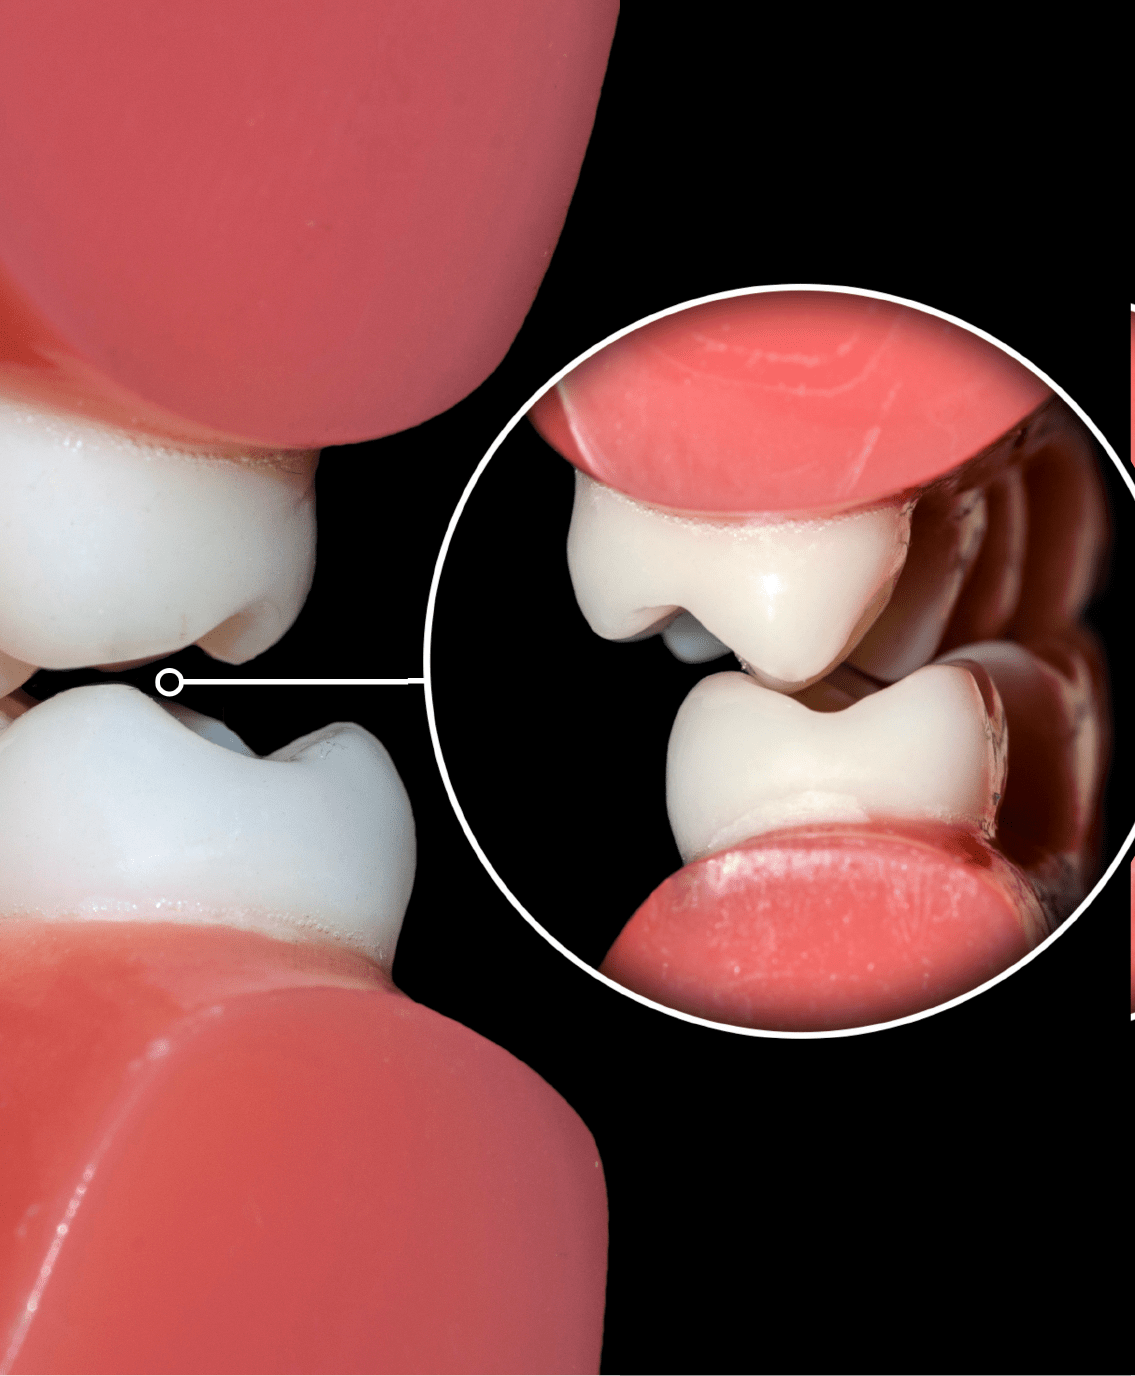

Occlusion is the relationship between your upper and lower arches of teeth. Your bite should be even with teeth aligned in such a way that no tooth bears undue pressure. A misaligned bite, or improper occlusion, can cause multiple problems including temporomandibular joint disorder, also known as TMJ or TMD.

Grinding of teeth (also known as bruxism) and clenching of the jaw are two common types of bite habits which can cause damage to your teeth. Grinding your teeth can wear down your enamel and change the shape of your teeth. Clenching causes too much pressure to build up by squeezing the teeth, which can lead to an actual cracked or broken tooth.

When teeth show wear, looseness, spacing (gaps between teeth), or shifting (called bite collapse), and/ or when damage/ pain occurs in TMJ (jaw joint) . The latter is also called TMJ Disorder (TMD).